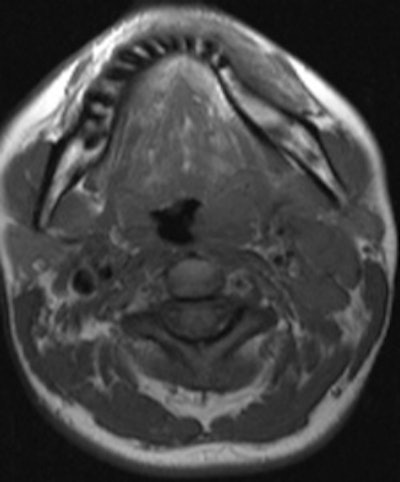

A 30-year-old woman suffering from oropharyngeal tularemia. She presented with painful left-sided cervical mass. Hypertrophic left palatine tonsil (arrow), narrowing oropharynx, isointense on T1-weighted and hyperintense on T2-weighted images compared with striated muscle with homogeneous contrast enhancement is seen on axial TSE T1-weighted (left), short tau inversion recovery (right). All images courtesy of Dr. Safiye Gürel."Radiologists should be aware of tularemia, especially in endemic areas. Usually unilateral, or bilateral in advanced cases, lymphadenopathies associated with hypertrophied lymphoid tissue are the most suspicious findings from a radiological point of view," Dr. Safiye Gürel told AuntMinnieEurope.com. "In advanced cases, the addition or presence of accompanying significant necrosis in lymph nodes and painful soft-tissue swelling is helpful in differentiating a case from tuberculosis or malignancy."